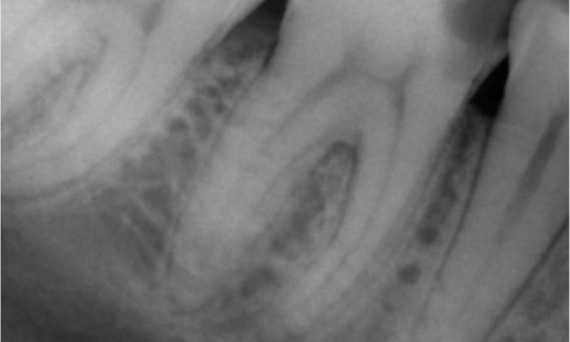

Before: Upon examination, there was a caries lesion related to the lower right first molar. Radiographic examination revealed proximity of the lesion to the pulp horn and combining it with the chief complaint, a final diagnosis of chronic irreversible pulpitis was concluded.

After: Access cavity was done as conservative as possible. TruNatomy was the system of choice due to the young patient’s age. We needed to preserve dentine as much as possible to increase the tooth ability to overcome occlusal load and increase the longevity of the final restoration.

Cairo, Egypt